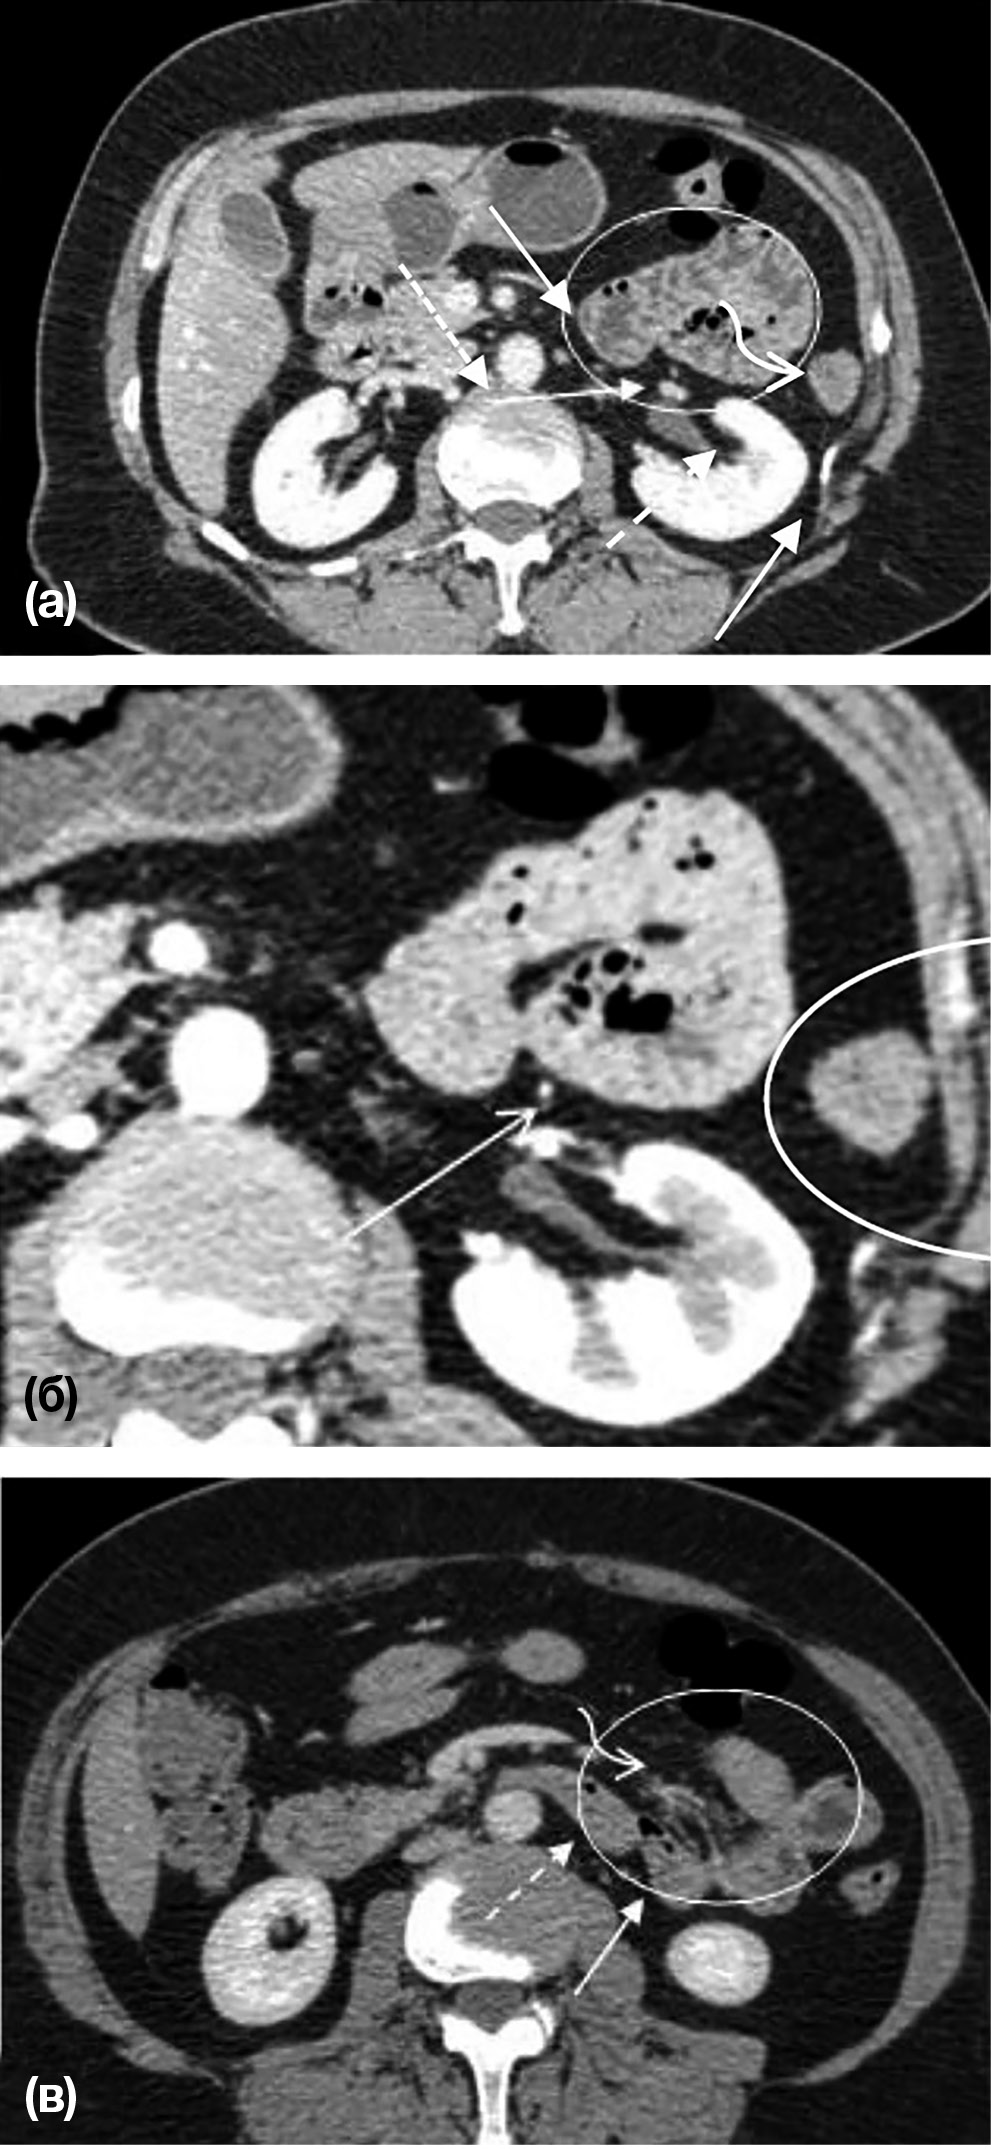

Рис. 5. Пациент А., 60 лет. Формирование грыжи отверстия Винслоу

Примечание. Отмечается избыточное скопление жира в брюшной полости, что вызывает повышенное внутрибрюшное давление. Петли кишечника (стрелки) находятся у свободного края малого сальника без проникновения в его полость. Пунктирной стрелкой обозначена воротная вена.

В одном из случаев мы наблюдали формирование грыжи отверстия Винслоу. Данные КТ демонстрируют, как к отверстию Винслоу смещены умеренно расширенная петля тонкого кишечника и толстая кишка, при этом проникновения в полость малого сальника не отмечалось (рис. 5).